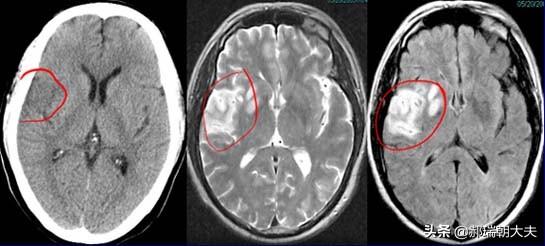

- しかし、臨床像の違いに加えて、時に臨床症状だけでは診断はできないまた、以下のような画像検査も行う。頭蓋CTと頭蓋MR.ラクナ梗塞にせよ脳梗塞にせよ、脳組織が虚血・低酸素状態にあるだけで、梗塞脳組織の液状化壊死はないため、24時間以内の頭部CTでは大きな変化はない。24時間以内であればある程度判別可能である。症状の急性期には、臨床では頭蓋MRが検査の第一選択となる。 MRIには様々なシーケンスがあり、症例によって異なるMRIシーケンスを用いて適切な検査を行うことができる。脳梗塞の診断において、DWIシーケンスは状況を明らかにするのに非常に直感的である。。

(3)検査:頭部のCT検査または核磁気検査。核磁気検査が最もよく、脳の対応する部分に空洞病巣を見つけることができる。

医学的定義では、ラクナ脳梗塞とは、大脳動脈から枝分かれした1本の細い血管の閉塞によって引き起こされる非皮質性の小さな梗塞である(梗塞病変の直径は通常0.2~15mm)。すなわち、ラクナ脳梗塞は、小さな動脈血管の閉塞によって引き起こされる脳の深部(非皮質)の小さな梗塞である。

海綿状脳梗塞

小動脈閉塞性脳梗塞の一種で、多くは高血圧、糖尿病などの基礎疾患により、脳の深部貫通動脈の虚血性微小梗塞で起こる。病変後に血管壁が閉塞し、虚血性梗塞が不規則な微小空洞を残すため、ラクナ脳梗塞と呼ばれる。

脳梁性脳梗塞は無症状の人もおり、頭蓋骨のCTやMRI検査で発見されることが多い:

脳出血と脳梗塞は症状が同じであり、症状から判断することはできないので、脳梗塞とラクナ脳梗塞の診断は、脳CTや脳MRIでさらにはっきりさせる必要がある。